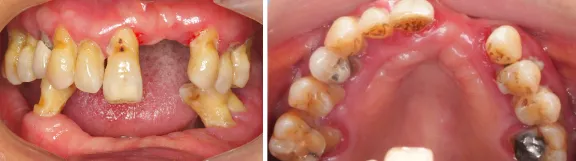

- 口腔卫生较差,21、22、27、31-33、35-37、41-45、47缺失,14金属烤瓷冠修复,16𬌗面汞充填,余牙松动Ⅲ,PD:5-8mm,BOP(+),牙龈萎缩,红肿,上下颌位关系正常,但无稳定的颌位关系。

口内检查上下颌多牙缺失